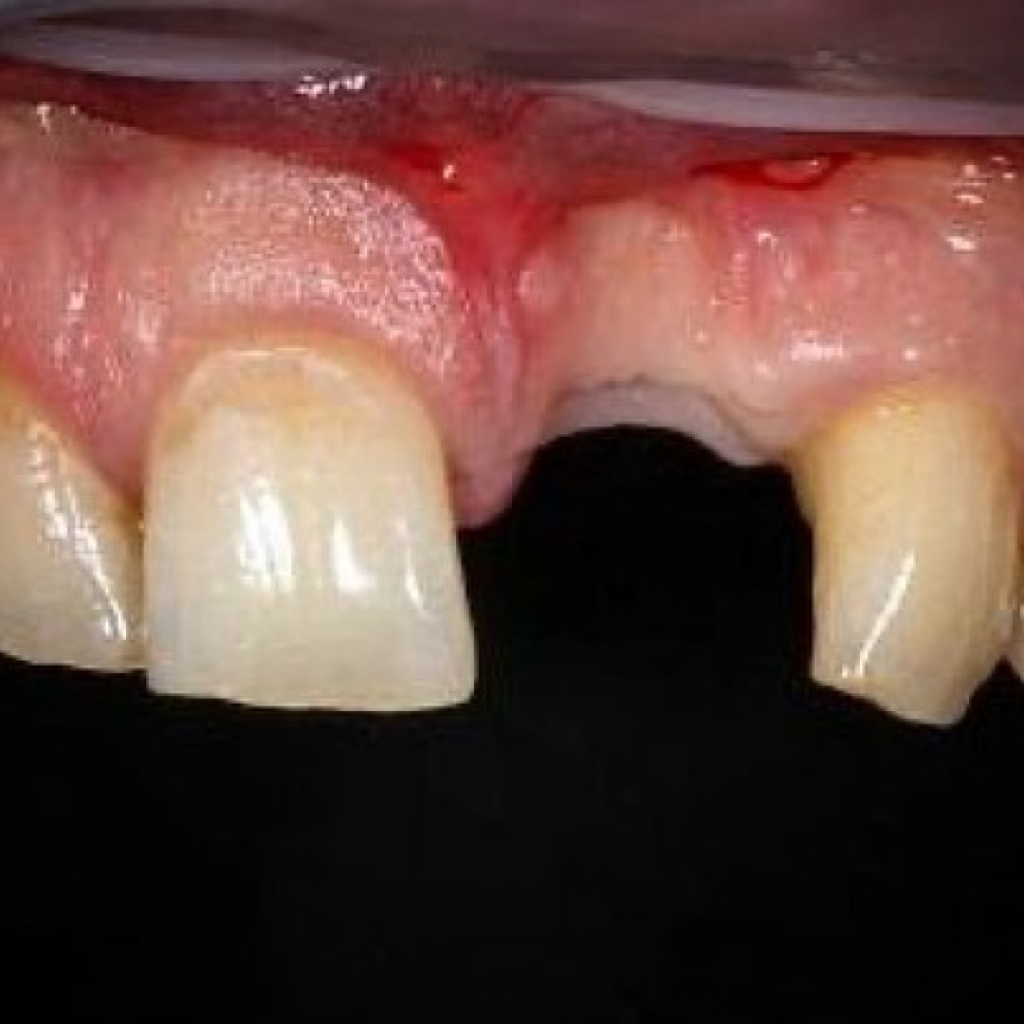

- Пациент Н. обратился с эстетическим и функциональным дефектом во фронтальной области верхней челюсти - отсутствует левый центральный резец, зуб 2.1

- Из анамнеза: в виду долгого ношения съемного протеза «бабочка», отмечается значительная атрофия костной ткани с вестибулярной стороны (со стороны верхней губы), соответственно, десневой контур также нарушен.